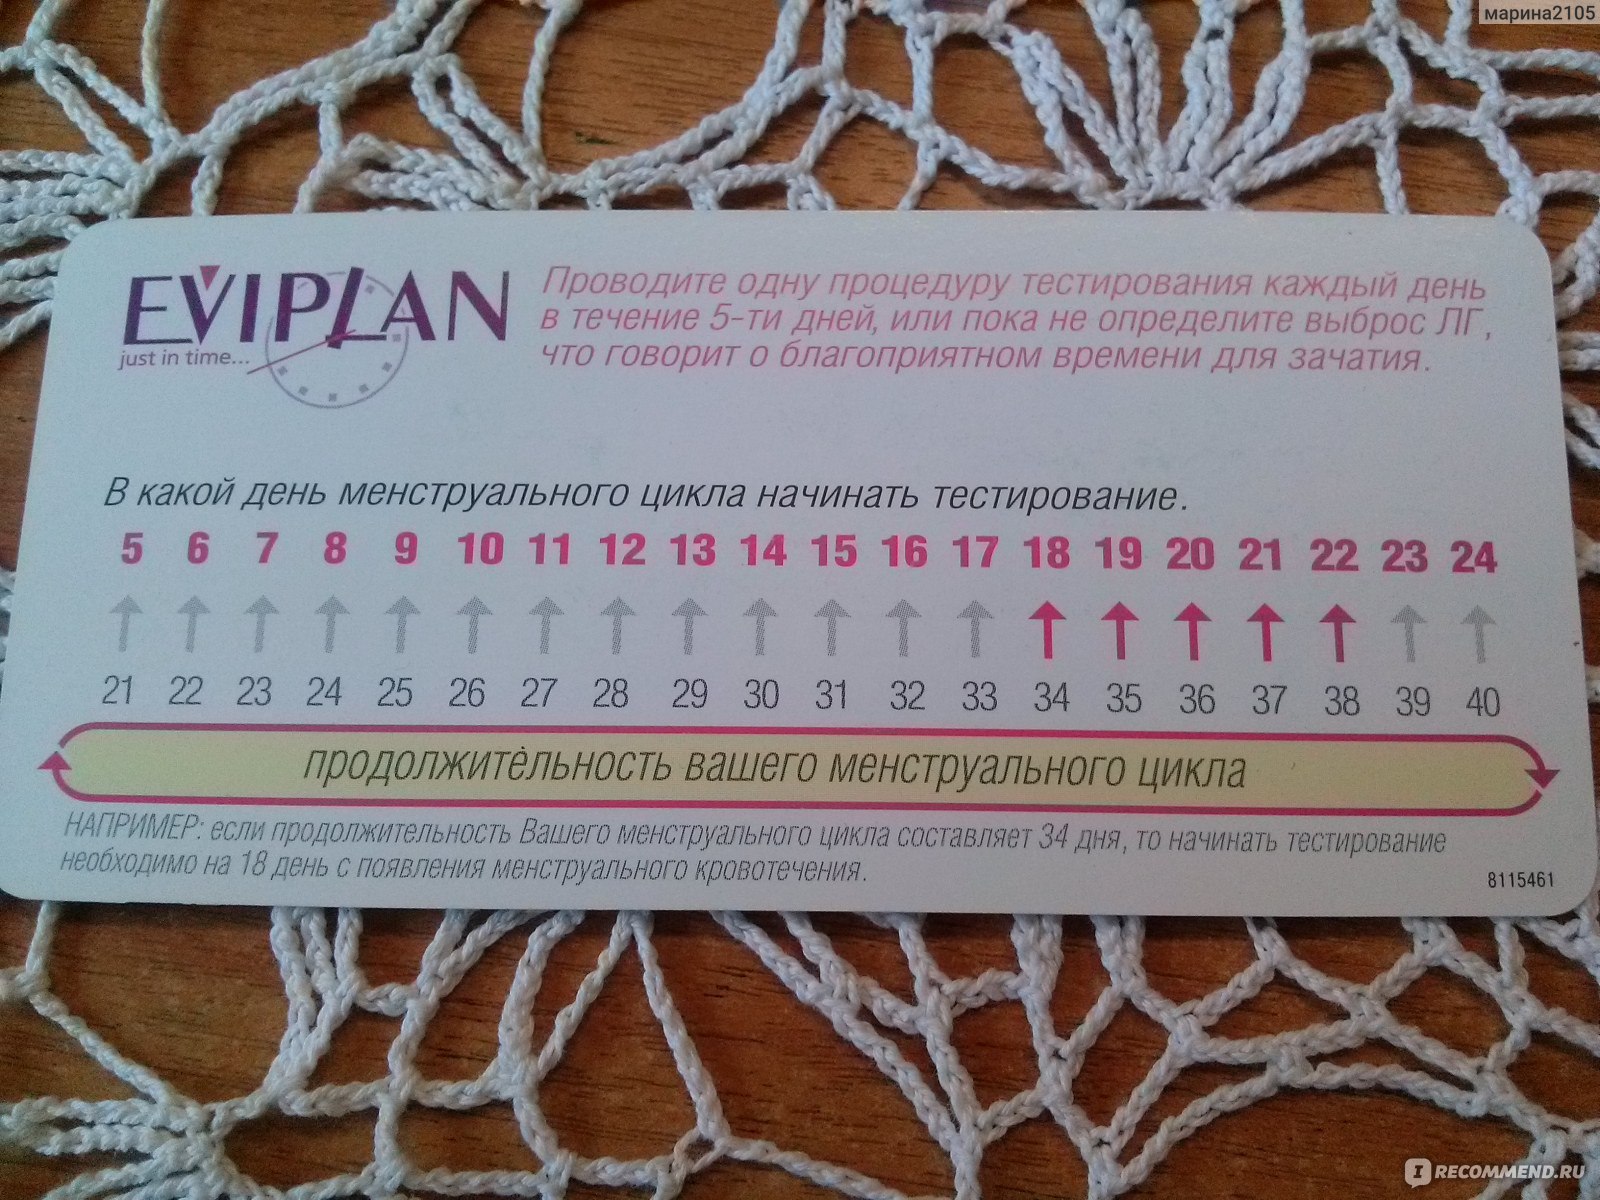

Рекомендации по зачатии